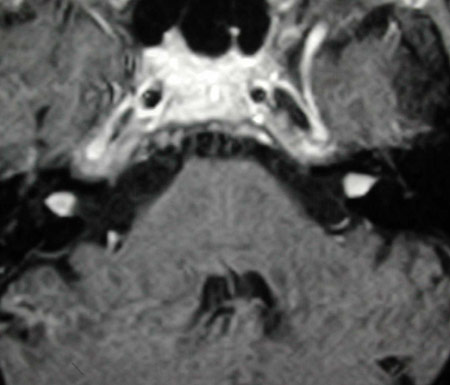

The vast majority (95%) of these tumors are sporadic, meaning they are not passed on through genes. Sporadic tumors occur in only one ear, and there are no known risk factors. Rarely these tumors are associated with a genetic disease called Neurofibromatosis Type II. Patients with Neurofibromatosis develop tumors at a younger age, usually have tumors on both sides and also have other manifestations, including benign tumors of the brain and dura (the covering of the brain).

MRI showing bilateral vestibular schwannomas